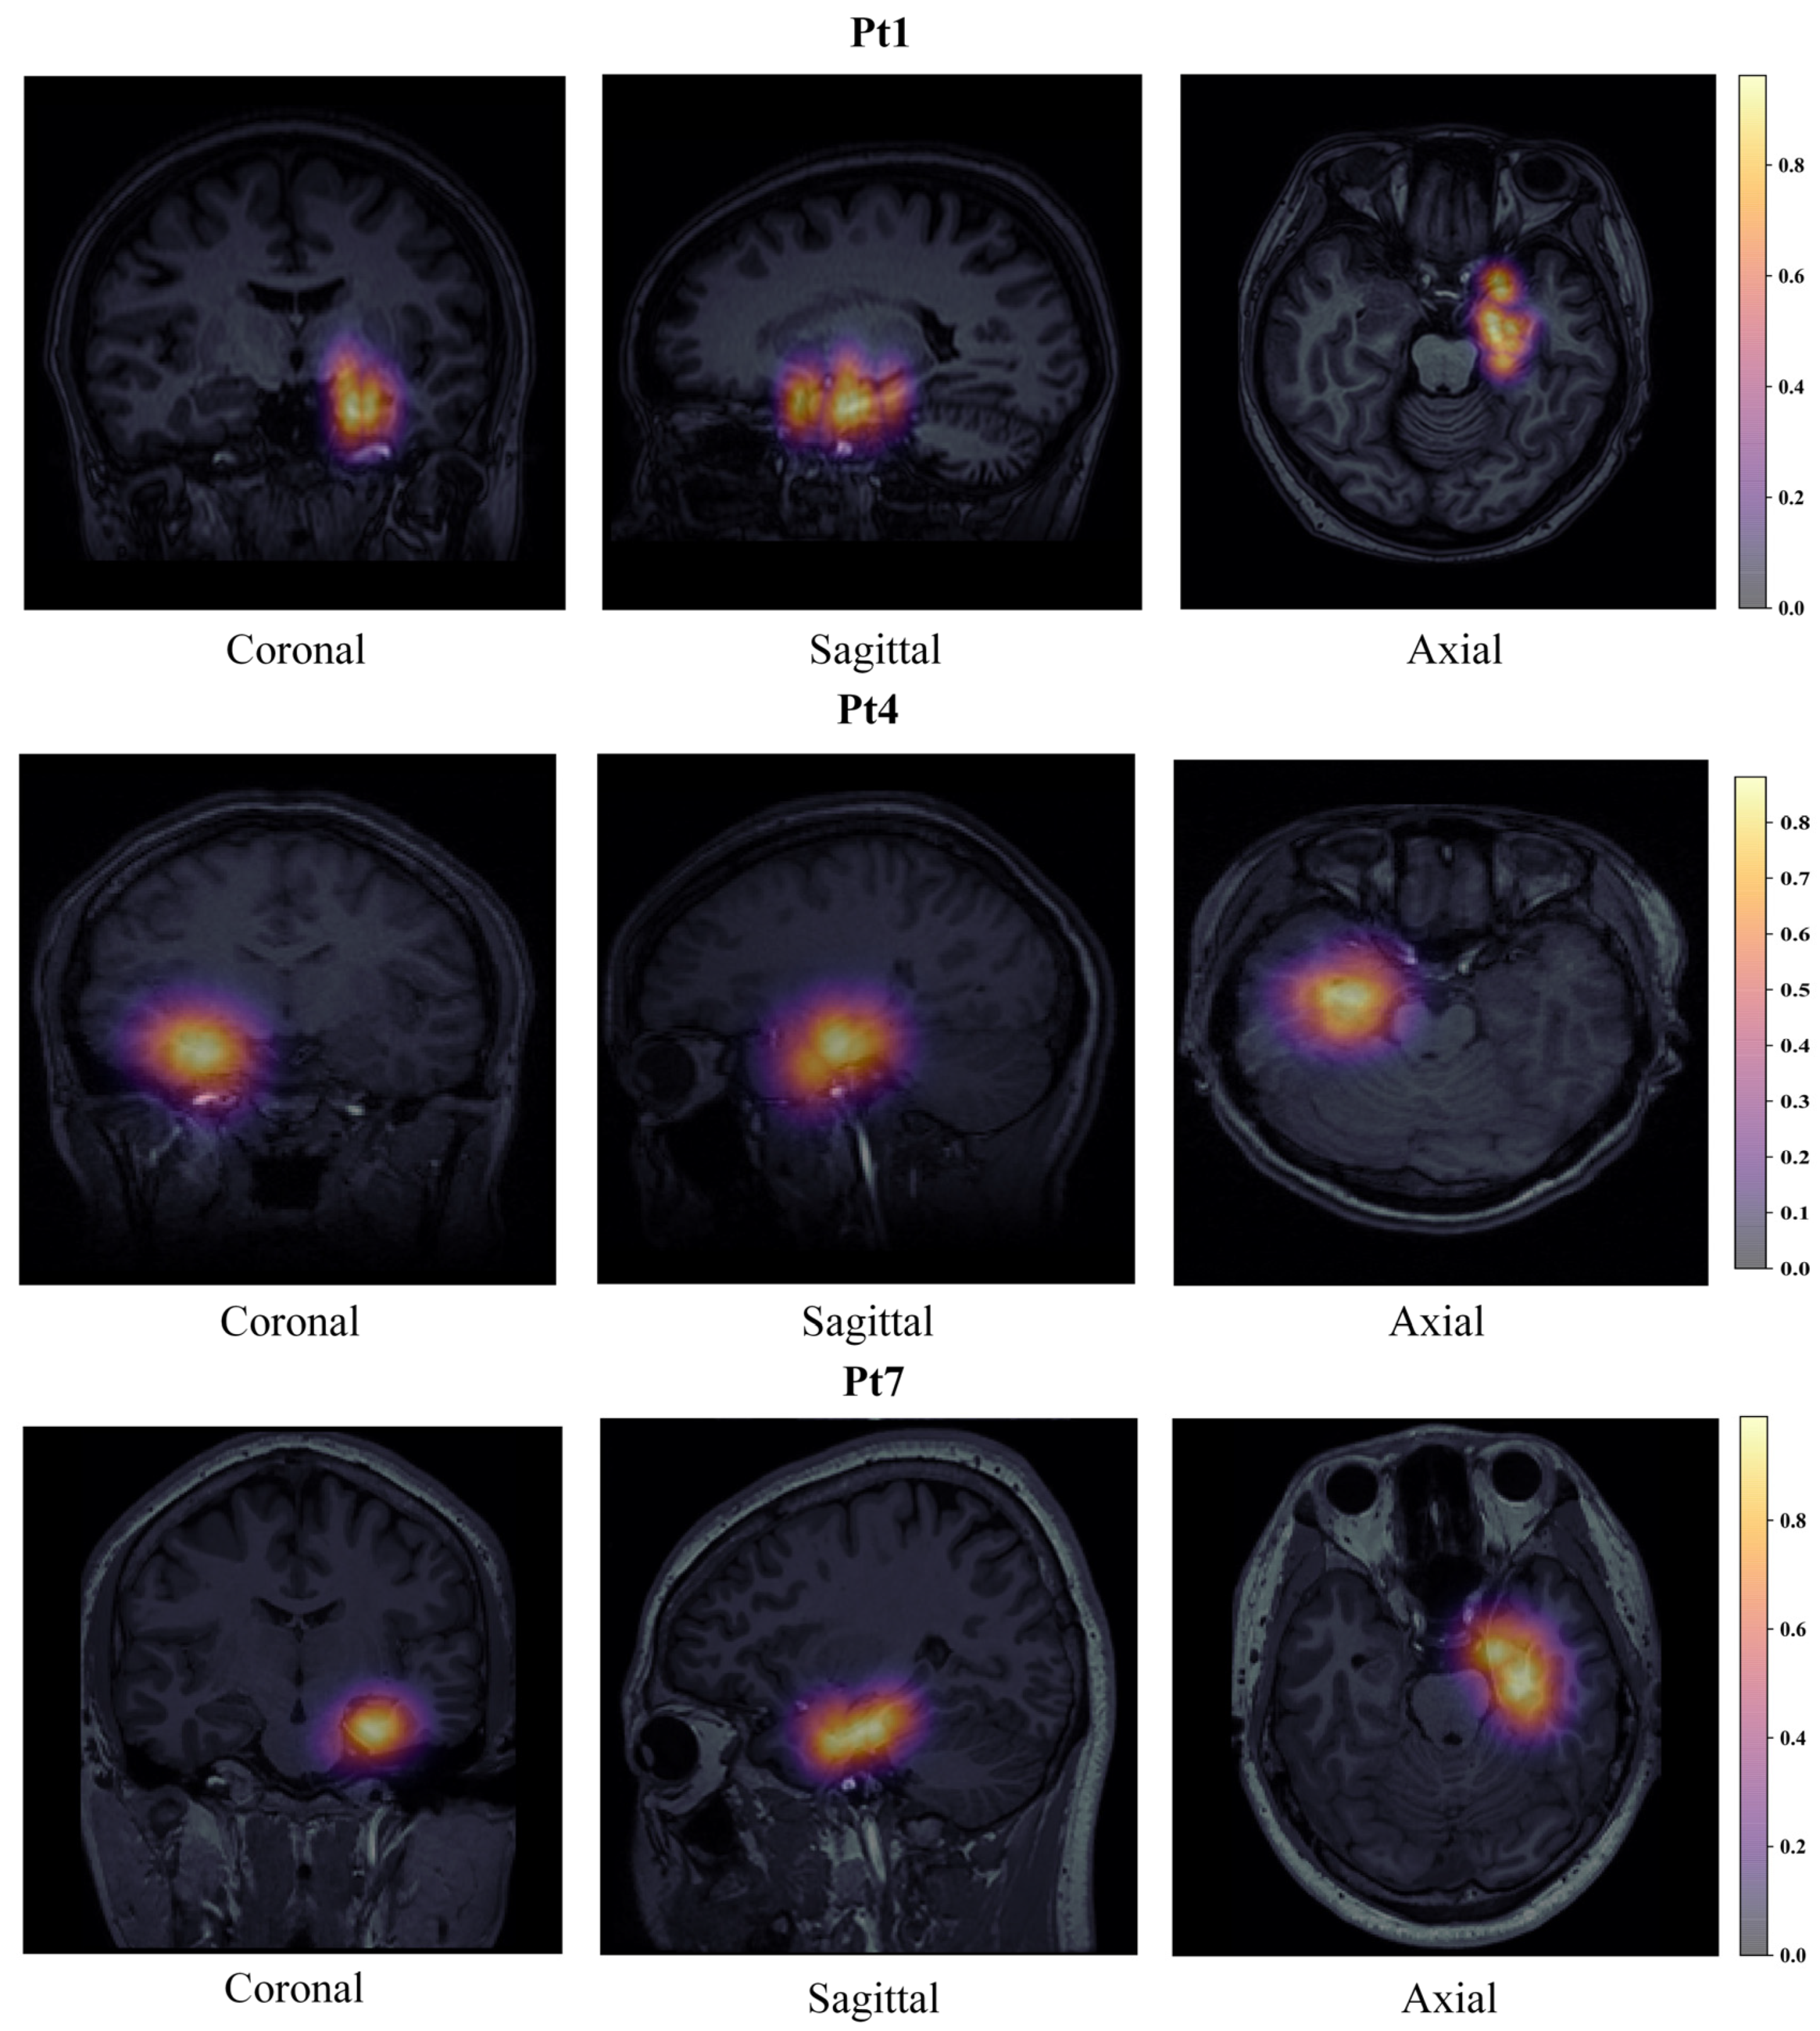

2.5. Individualized SOZ Prediction and Visualizaiton

- Considering the low correlation between brain boundary voxels and SOZ, this section set brain boundary voxels to the lowest quantified value;

- Considering the strong correlation between the SOZ surrounding voxels and SOZ contacts, we set SOZ contacts and their surrounding voxels to the predicted value corresponding to the contact;

- To further achieve whole-brain mapping, we used a 3D Gaussian kernel method to map all other voxels in the whole brain. The other voxels’ values are between the predicted values of the SOZ surrounding voxels and the quantified values of the brain boundary voxels;

- The predictive values of all voxels were calculated through the above interpolation method, ranging from 0 to 1. Then, we visualized the predictive values on the MRI. Thus, individualized SOZ prediction and visualization were obtained.

4.4. Visualization of Electrodes with MRI